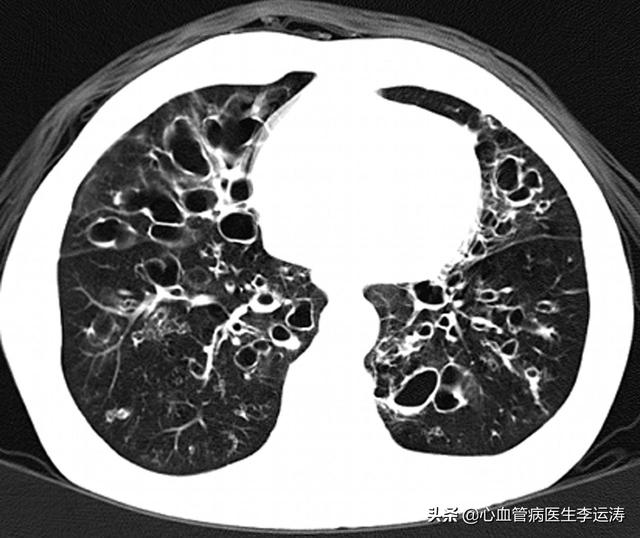

比如这次的新冠肺炎,如果没有化验检查,根据经验,可能就当成普通的病毒性肺炎来治疗了,正是有了这些化验检查,我们才能找到致病微生物,发现疾病的本质,更好的治疗疾病。